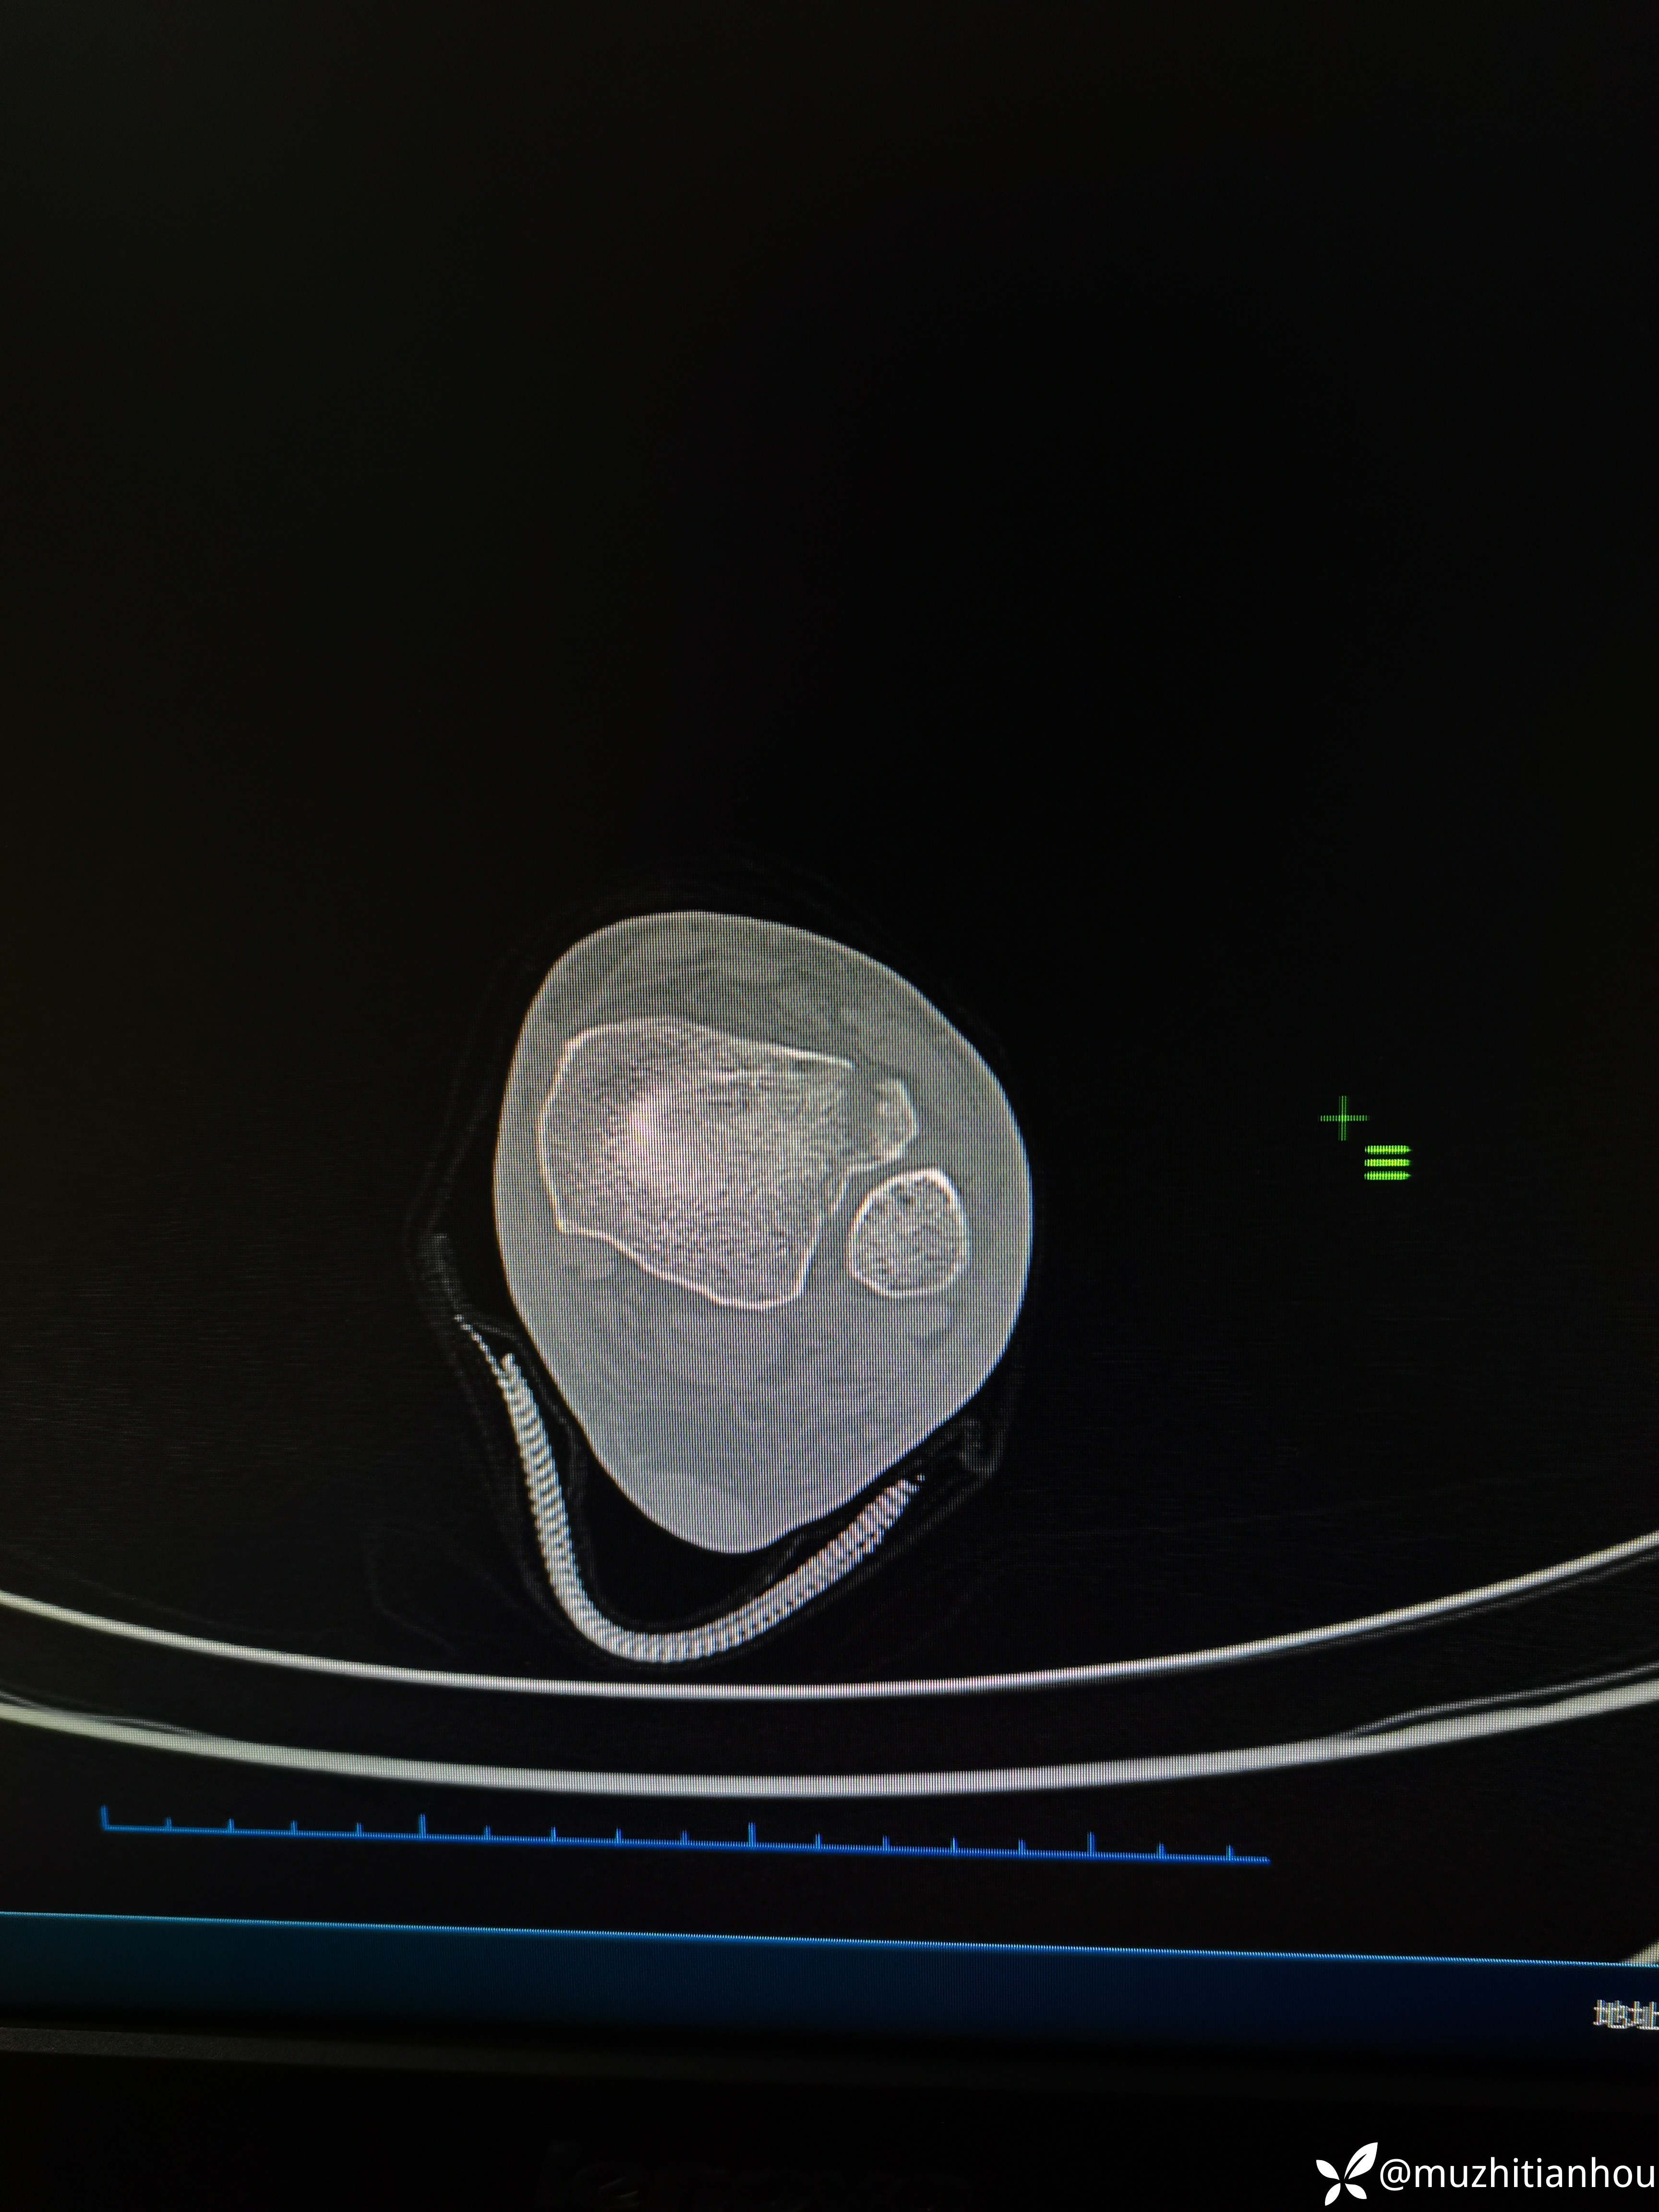

讲明白道理后取得患者信任,入院做了三维CT真像慢慢浮出水面,看到这个您是不是觉得收获很大

后踝骨块无需处理

三维重建来的更直观,Tillaux骨块的分型和处理选择大家是否铭记在心呢?我想大多数人跟我差不多,回头去复习下吧。收获会很大

沈通氏线中段,tillaux骨块累及到下胫腓